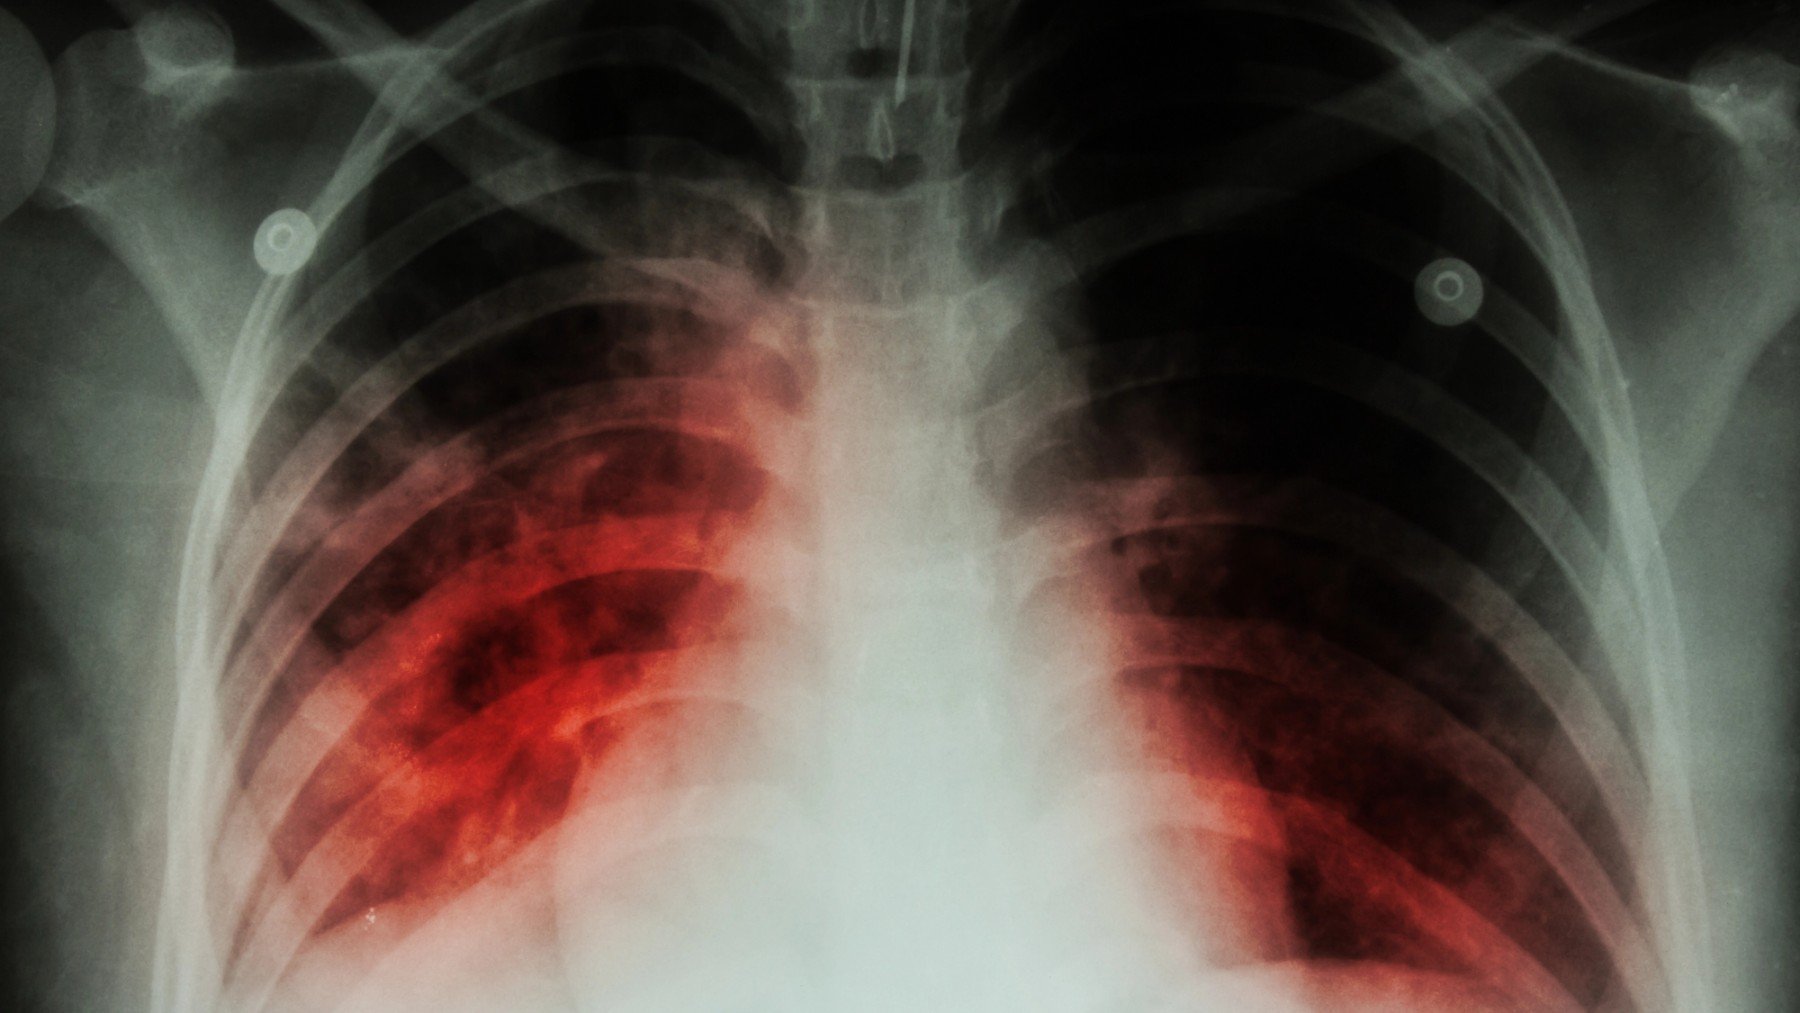

El Dr. Arnaiz: «La nueva estrategia contra la tuberculosis resistente es más corta y totalmente oral»

Francisco Arnaiz ha presentado evidencias prometedoras sobre el uso de nuevos antibióticos frente a infecciones graves por bacterias multirresistentes...